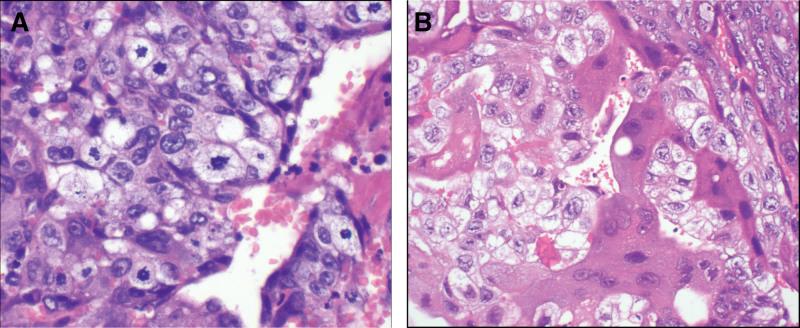

Delayed postpartum hemorrhage is rare, with an incidence of 0.5% to 2.0% in all pregnancies. The most important causes are placental remnants, infections, and placental bed subinvolution. Postpartum choriocarcinoma, a highly malignant complication of pregnancy, is a rare condition that can be easily misdiagnosed as other common causes, such as gestational remnants, and delays the diagnosis.

Four patients visited our clinic complaining of delayed postpartum hemorrhage, combined with respiratory and neurological symptoms in 2 cases. Two cases were confirmed by histopathological examination and in addition, medical history, elevated human chorionic gonadotropin (hCG) level, and imaging findings help confirm the diagnosis of delayed postpartum hemorrhage caused by postpartum choriocarcinoma in other cases. Individualized combination chemotherapies were prescribed. In the light of massive cerebral metastasis in case 2, intrathecal methotrexate injection combined with whole-brain radiotherapy was prescribed.